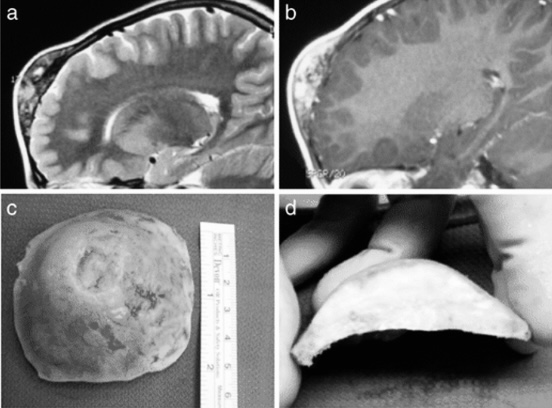

▼脑瘤凶猛侵袭▼ 短短4年,遭遇4次复发,每次复发都伴随着肿瘤的一再恶化。Ki-67指数更是从1%飙升至30%!7岁孩童究竟遭遇了什么骇人脑瘤,他又是如何逃出生天的? 额骨肿块揪出脑瘤谜团...

孩子开颅手术后能恢复到从前吗? 开颅术后1年多,小欧的随访报告再一次带来了好消息。 我很高兴得知孩子目前没有明显症状,也很欣慰看到他的视频,可以看出他现在是个完全正常的孩子。...